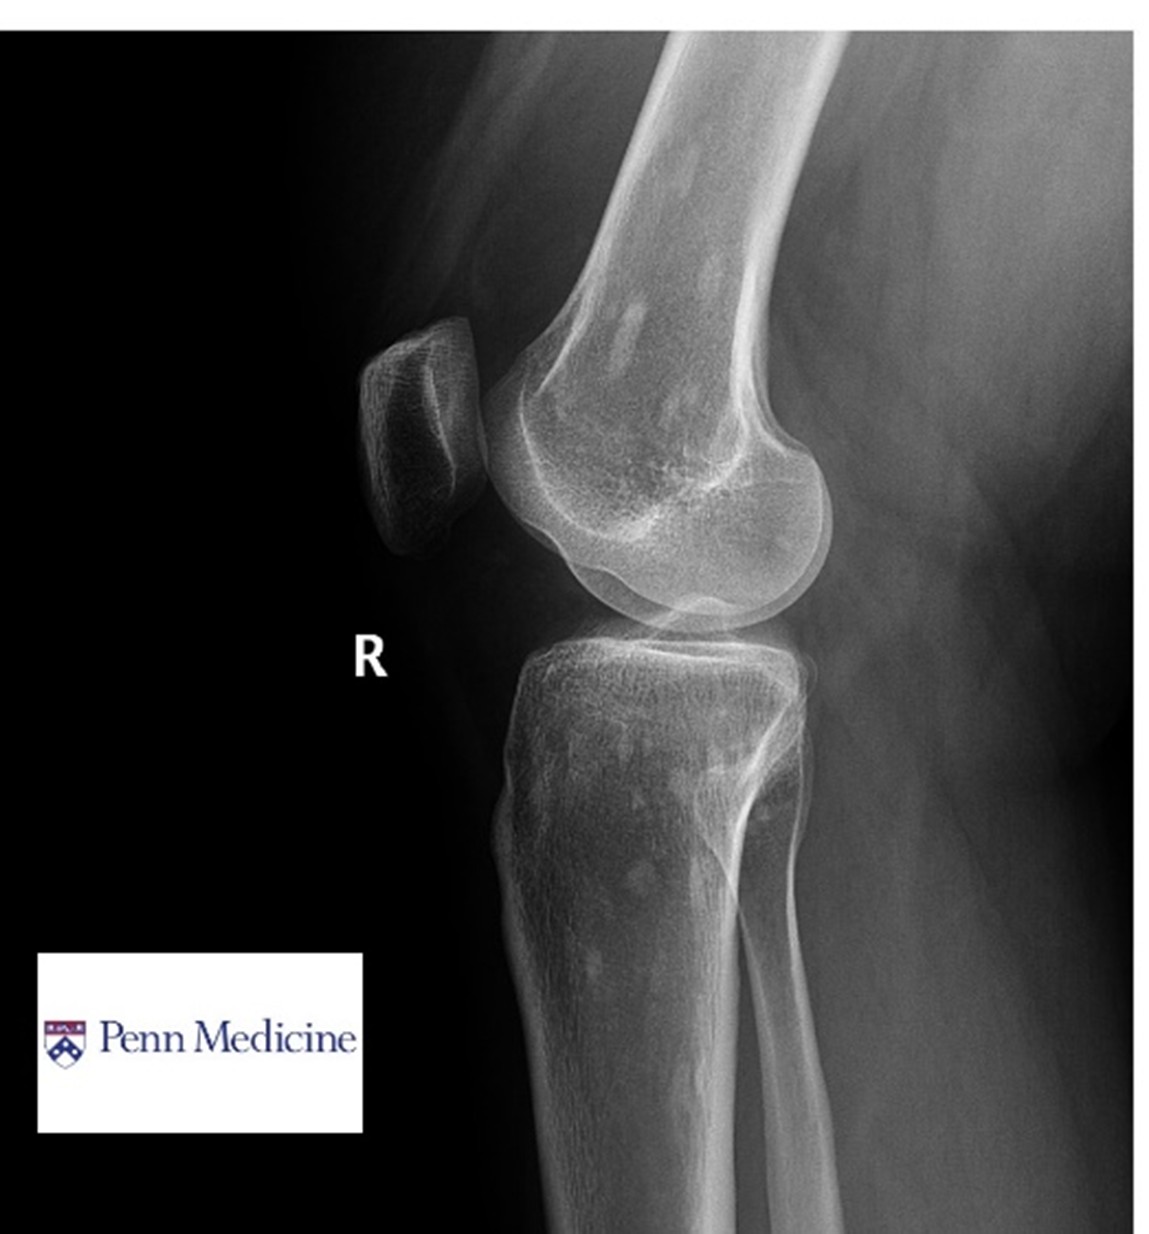

Cases of the Week

Check out our Cases of the Week!